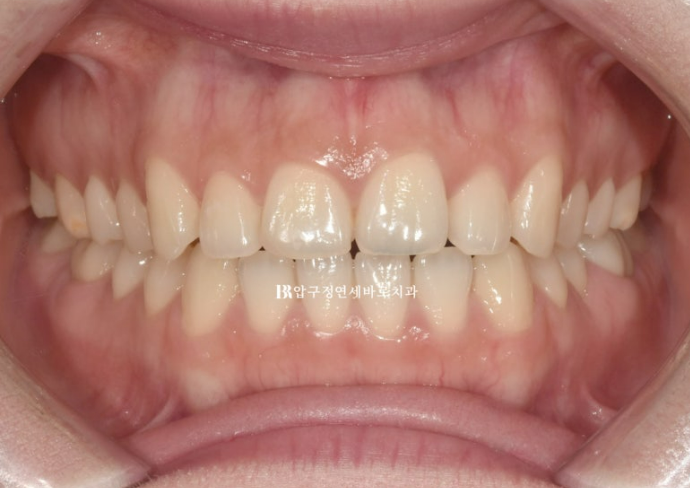

무삭제 라미네이트 치료를 위해 찾아오신 환자분입니다.

오래전 교정치료를 완료한 상태이고 그간 유지장치가 떨어지거나 하는 일들이 있었는 지 앞니 사이가 벌어져 있습니다.

이 환자분의 치료에서 주목할 점은 스마일라인 입니다.

환자분의 스마일라인을 보겠습니다.

치아를 이은 선이 일자죠?

이런 상태를 리버스 또는 플랫 스마일이라고 합니다.

웃을 때 뭔가가 어색해보이죠?